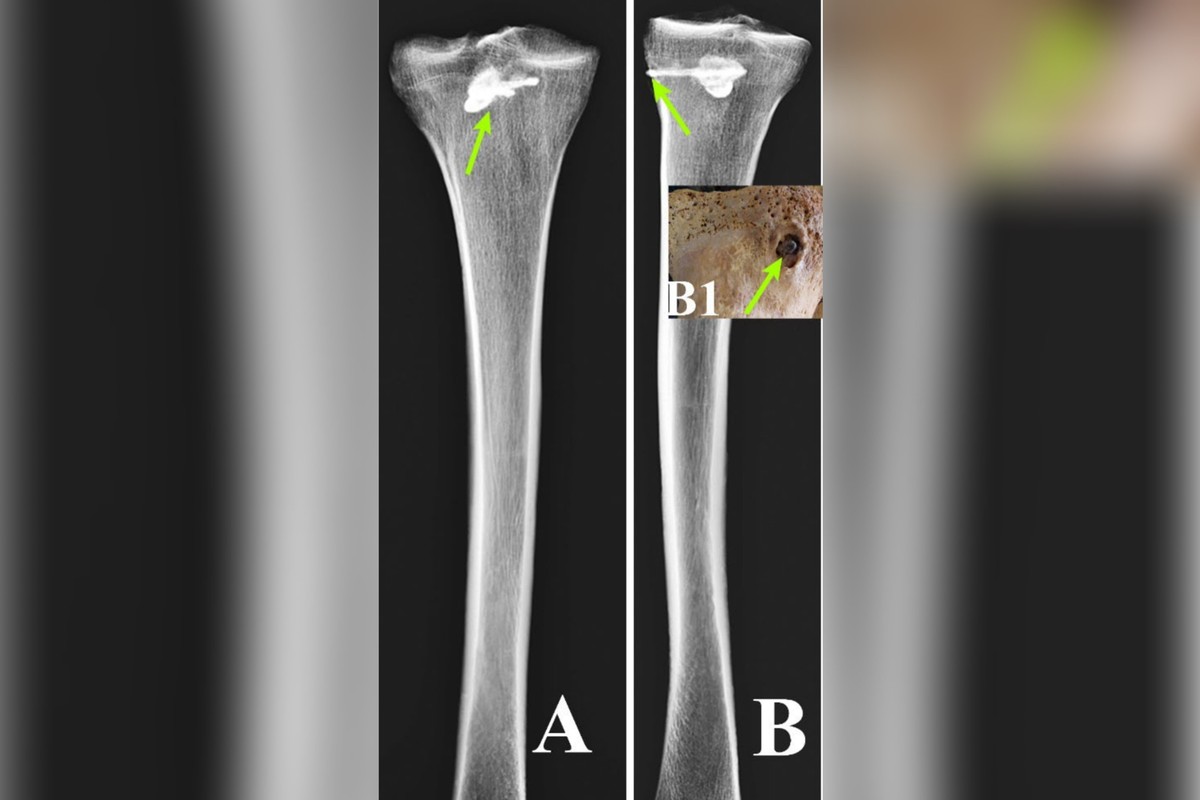

A ossada estava incompleta, sem partes da pélvis, costelas, vértebras e braço esquerdo. E, em sua tíbia, o homem carregava um flecha que não f...